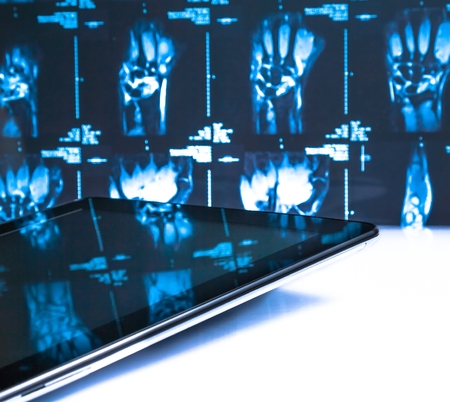

Medicine reflection in X-ray photography and mobile screen

modern digital tablet pc in laboratory on x-ray images background. concept of medical or research theme